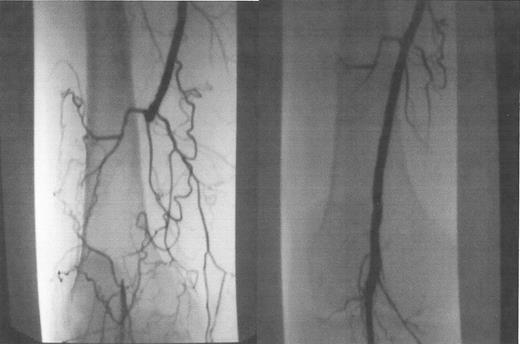

Occluded popliteal artery, before (A) and after (B) laser-assisted balloon angioplasty.